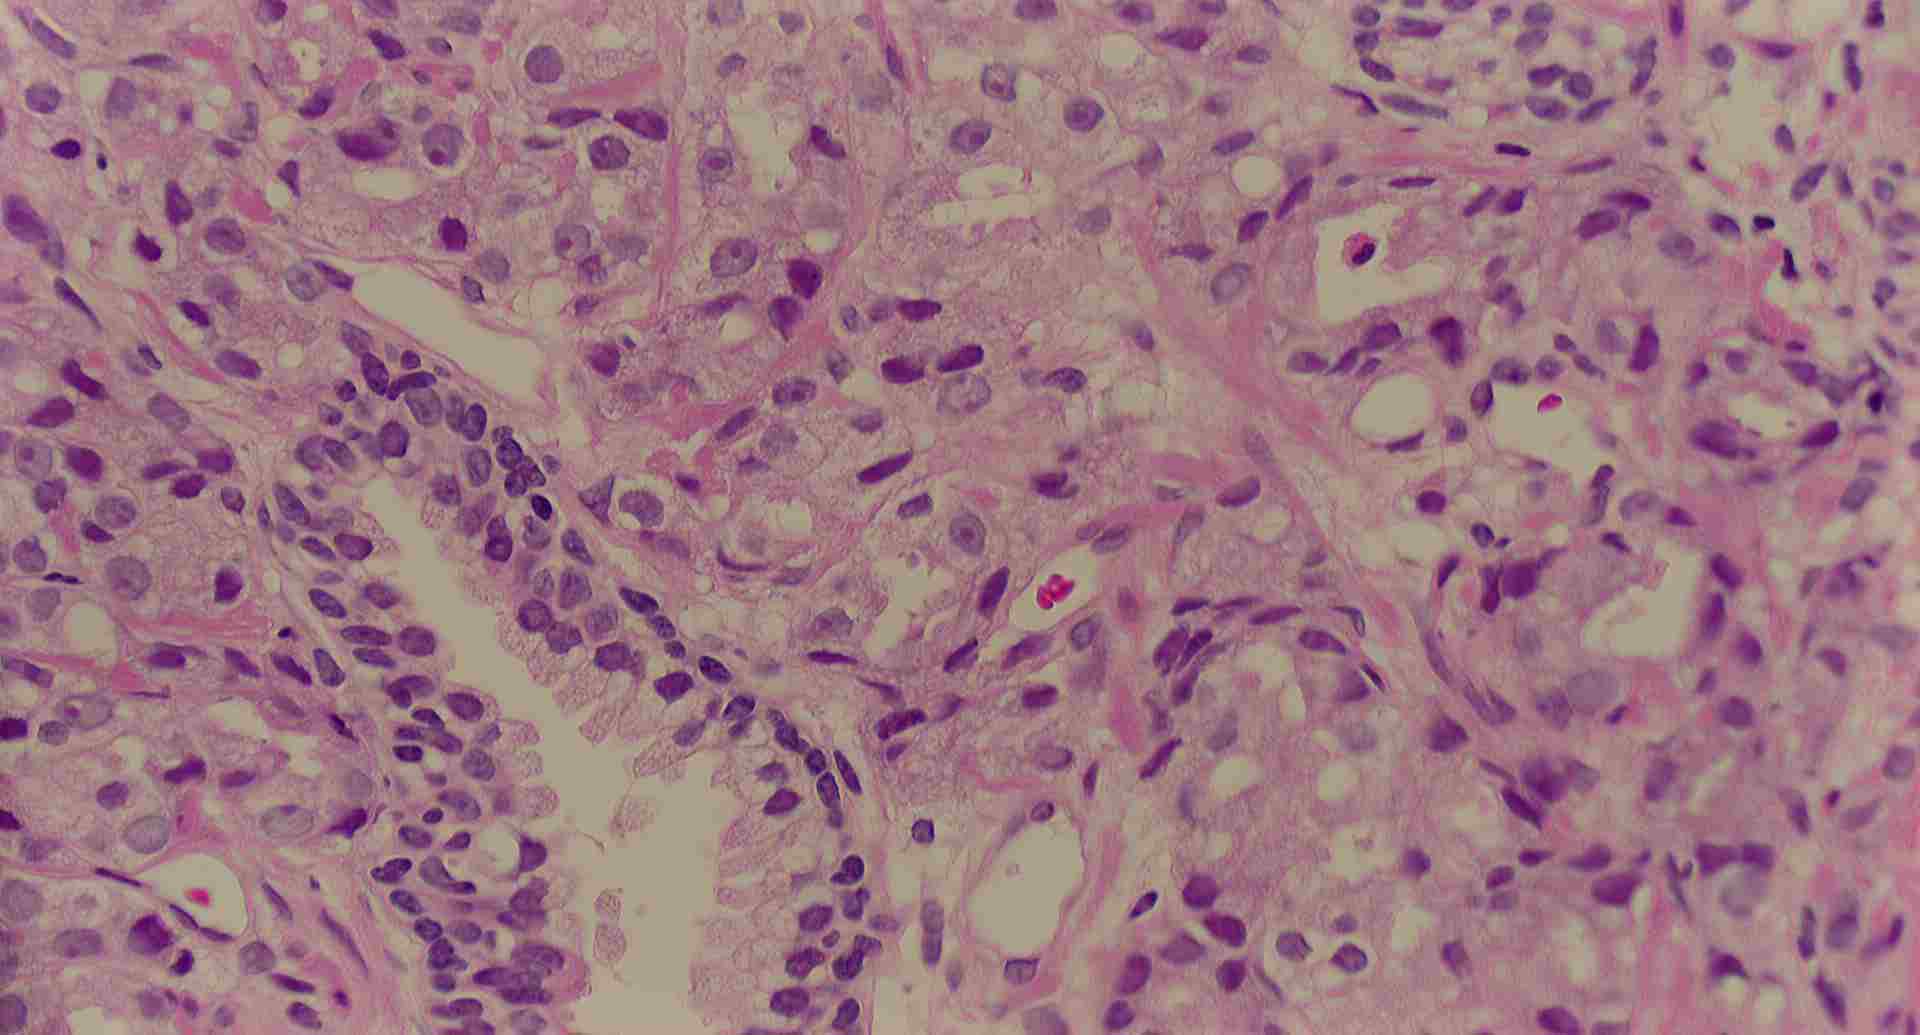

標本11

標本11の説明